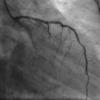

May 15, 2020 – A late-breaking study aimed to evaluate whether optical coherence tomography (OCT) can predict…